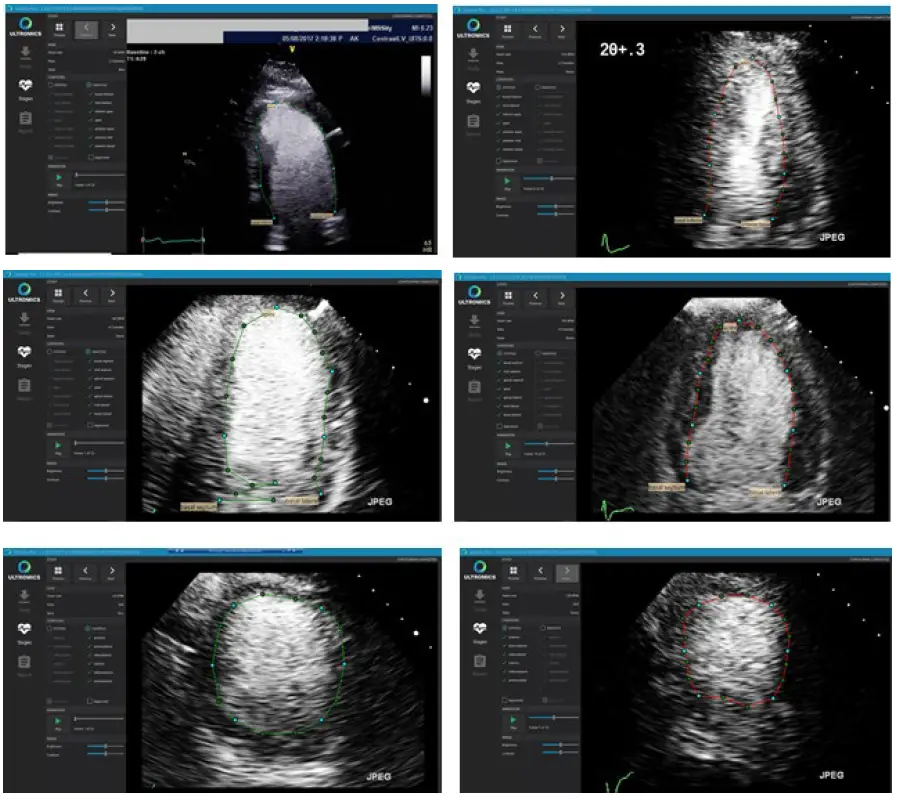

If a batch of received files pass the technical QC, the algorithm for automated contour detection of the endocardium of the LV (ROI’s) is applied. The auto-contouring is detected at end-systole (ES) and end-diastole (ED) for the apical two chamber (A2C), four-chamber (A4C) and mid-ventricular SAX views at both rest and peak stages. Appendix A provides examples of contours that shall be rejected and accepted.

Figure 2: Example of the contouring screen used to access the quality of the generated auto-contours

Any deviations detected by an operator shall be flagged on the system and reported. If auto-contours are of suboptimal quality for processing, they will be rejected, a rejection report will be generated and sent to the referring physician.

Contour Images: Accept

Contour Images: Reject